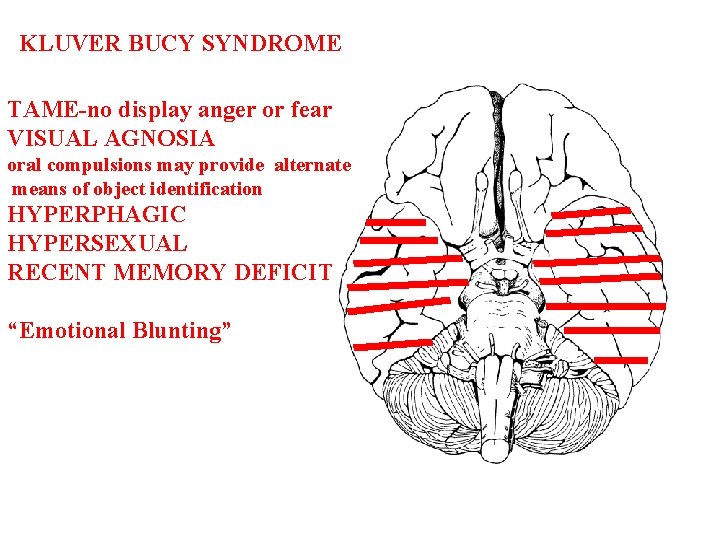

KLUVER BUCY SYNDROME TAME-no display anger or fear VISUAL AGNOSIA oral compulsions may provide alternate means of object identification HYPERPHAGIC HYPERSEXUAL RECENT MEMORY DEFICIT “Emotional Blunting”